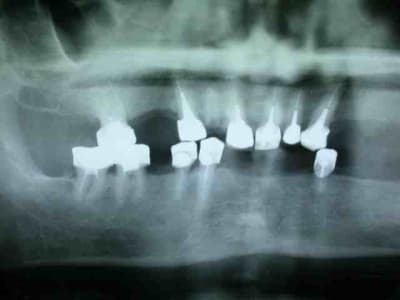

moulage panoramique...

bon allez je vous mets la pano initial et je continue après.